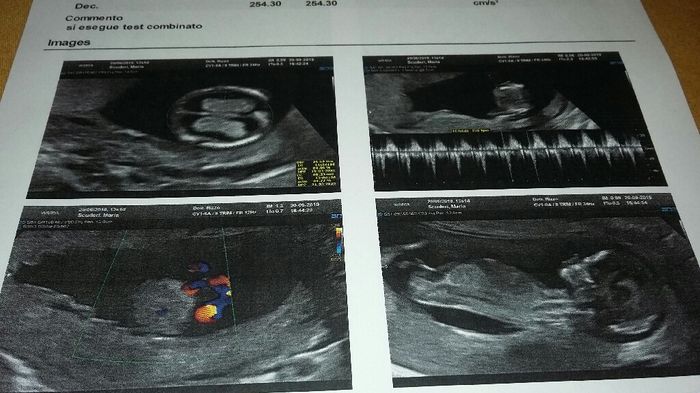

Buon giorno, ieri finalmente abbiamo rivisto il mio/a fagiolino/a e sentito il cuoricino battere......un emozione unica........... Giorno 20 settembre Translucenza nucale